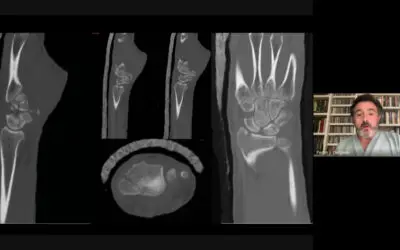

El vídeo corresponde a la tercera sesión de INCOT, titulada “Lo que (realmente) sabemos sobre el ligamento escafolunar”, presentada por Alex Lluch y el Dr. Gustavo Gómez. En esta sesión se analizan de forma crítica y actualizada los aspectos clave del ligamento escafolunar, aportando evidencia clínica, experiencias prácticas y discusión alrededor de su diagnóstico y tratamiento en el contexto de la ortopedia y traumatología.